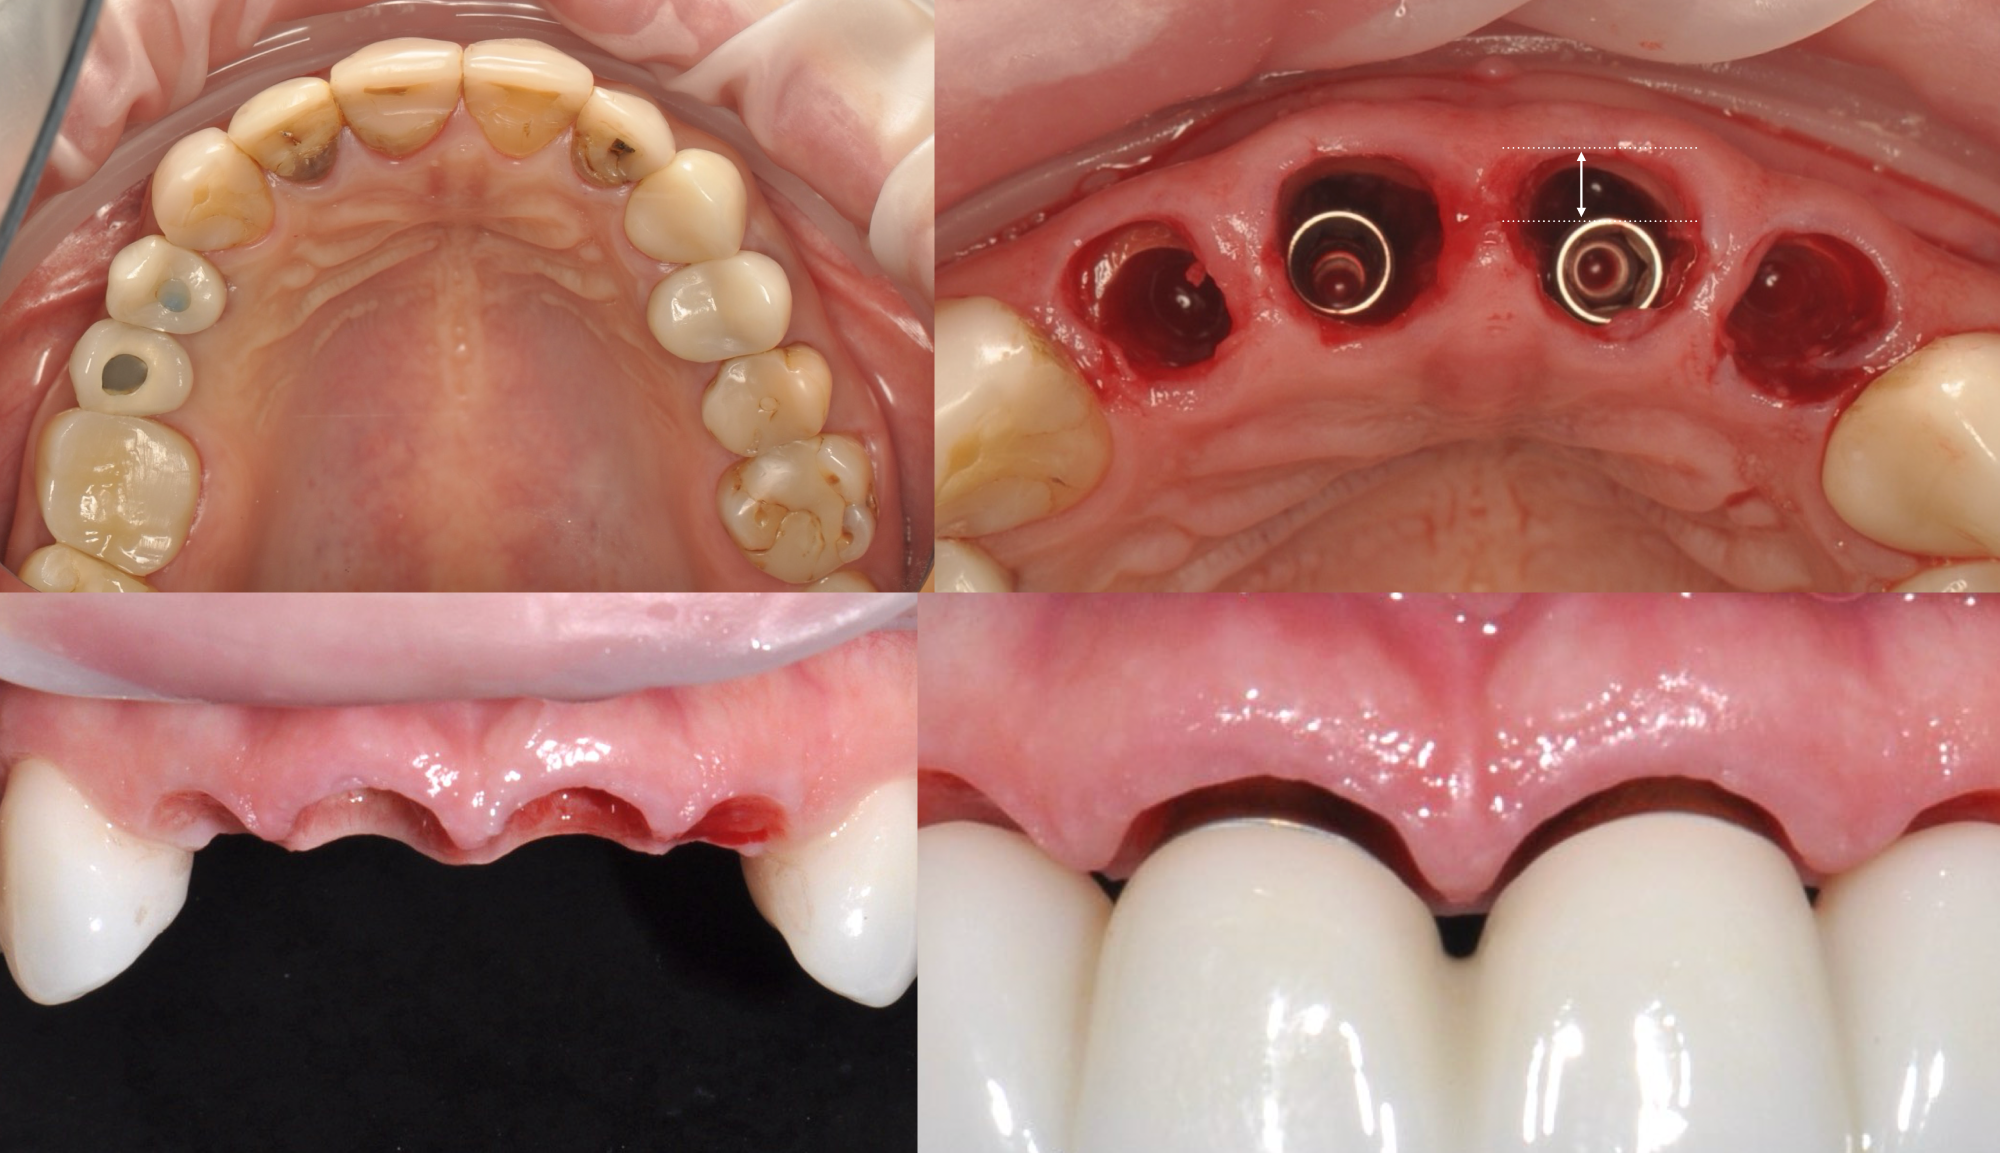

Implant-Supported Overdenture

• Overdenture concepts and prosthetic Principles

• Hands on Denture conversion

Director’s Clinical Cases

Implant-Supported Overdenture

• Overdenture concepts and prosthetic Principles

• Hands on Denture conversion

Director’s Clinical Cases